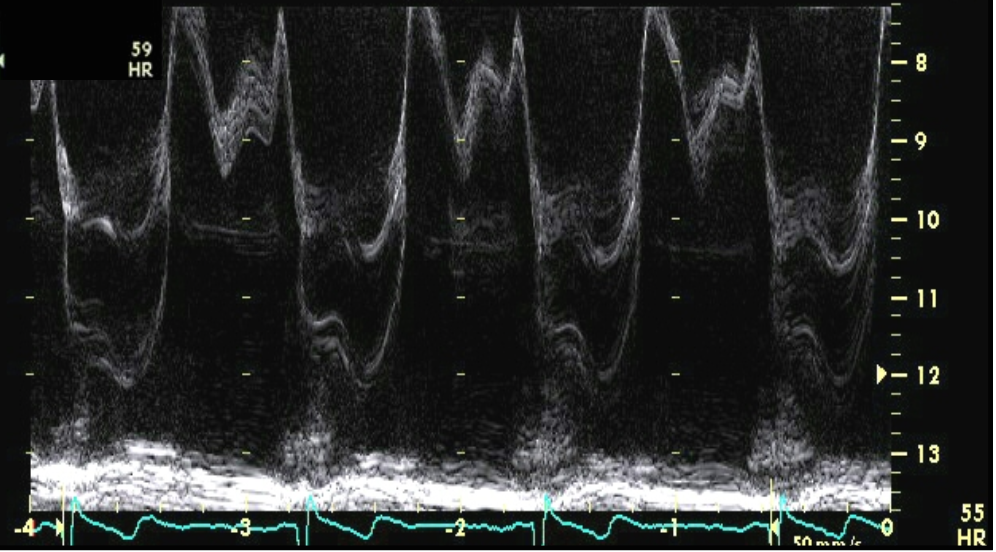

which MR is more severe?

the top one (more dense jet, holosystolic vs. end-systolic only)